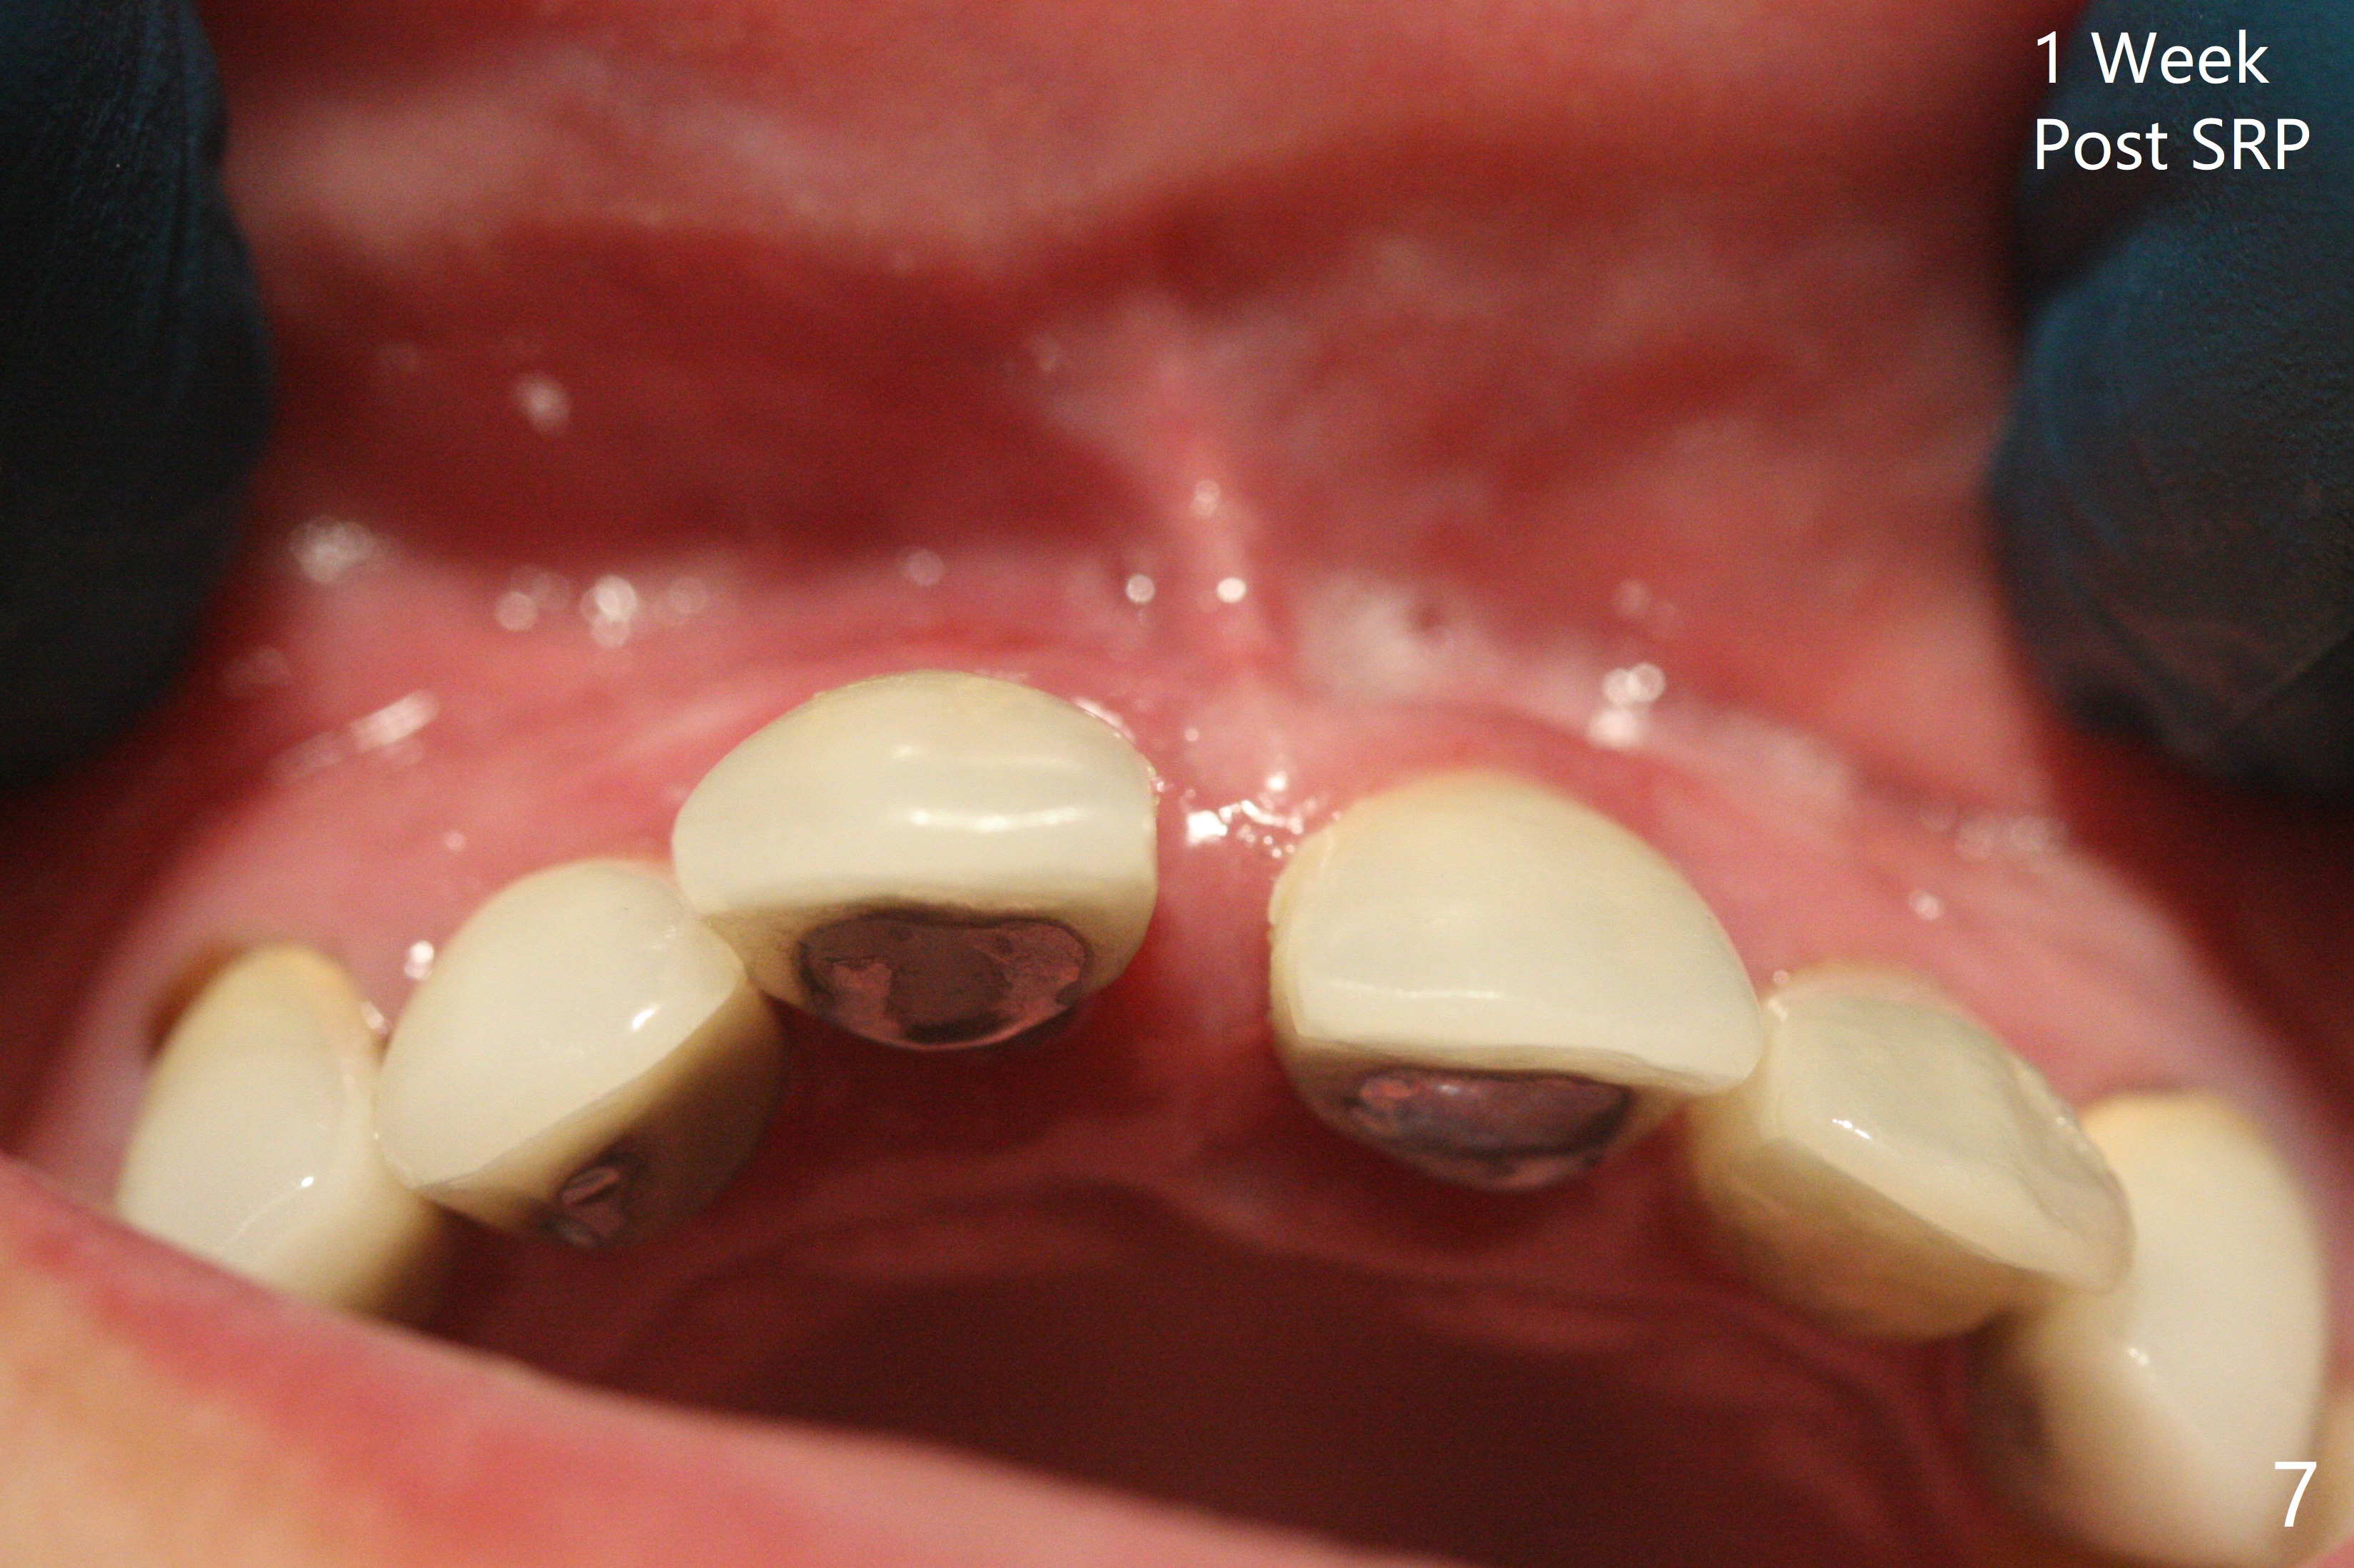

45岁女,害怕治疗,5年多没就医,右上1移位(图一(*),二),严重骨吸收(图三)。深洗后,即刻种植,由于牙龈7毫米长(图四,五)和使用粘性骨粉(骨壁再生),植体可以植浅些(图四:箭头)。上颌深洗一周后,除了患牙,牙龈红肿消除很多(图六,七)。